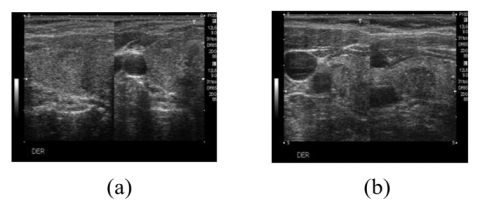

The Digital Database of Thyroid Images (DDTI) dataset, provided by Columbia National University, is used in this study to classify thyroid nodules [20]. This collection includes 480 US pictures from 400 thyroid illness patients. After ignoring the 480 faulty images, 427 US images are all that are left. Based on the placement of thyroid nodules in each class of the different (TI-RADS) standard, the thyroid pictures in this dataset are divided into six classes: 2, 3, 4A, 4B, 4C, and 5. According to the TI-RADS recognition concept, the classes "2, 3" are designated as benign nodules and "4A, 4B, 4C, 5" are designated as malignant nodules. Then, the sample images of benign and malignant nodules are shown in the Figure 2 (a) and Figure 2 (b) respectively.

Figure 2. Sample images: (a) Benign nodules; (b) Malignant nodules